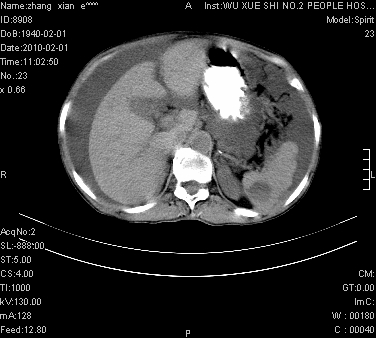

标题: CT24434:70岁 女 腹胀,腹水原因待查 [打印本页]

标题: CT24434:70岁 女 腹胀,腹水原因待查

大量腹水,脾脏囊性占位,子宫颈占位,右侧腹股沟淋巴结肿大,建议+c,先查妇科。

腹盆腔大量积液,子宫增大,子宫颈增大外形不规则,内见低密度影,膀胱后壁显示不清,右腹股沟肿大淋巴结,脾脏囊性占位,子宫颈占位,子宫颈癌?建议增强。

腹盆腔大量积液,子宫增大,子宫颈增大外形不规则,内见低密度影,膀胱后壁显示不清,右腹股沟肿大淋巴结,脾脏囊性占位,子宫颈占位,子宫颈癌?建议增强。支持!